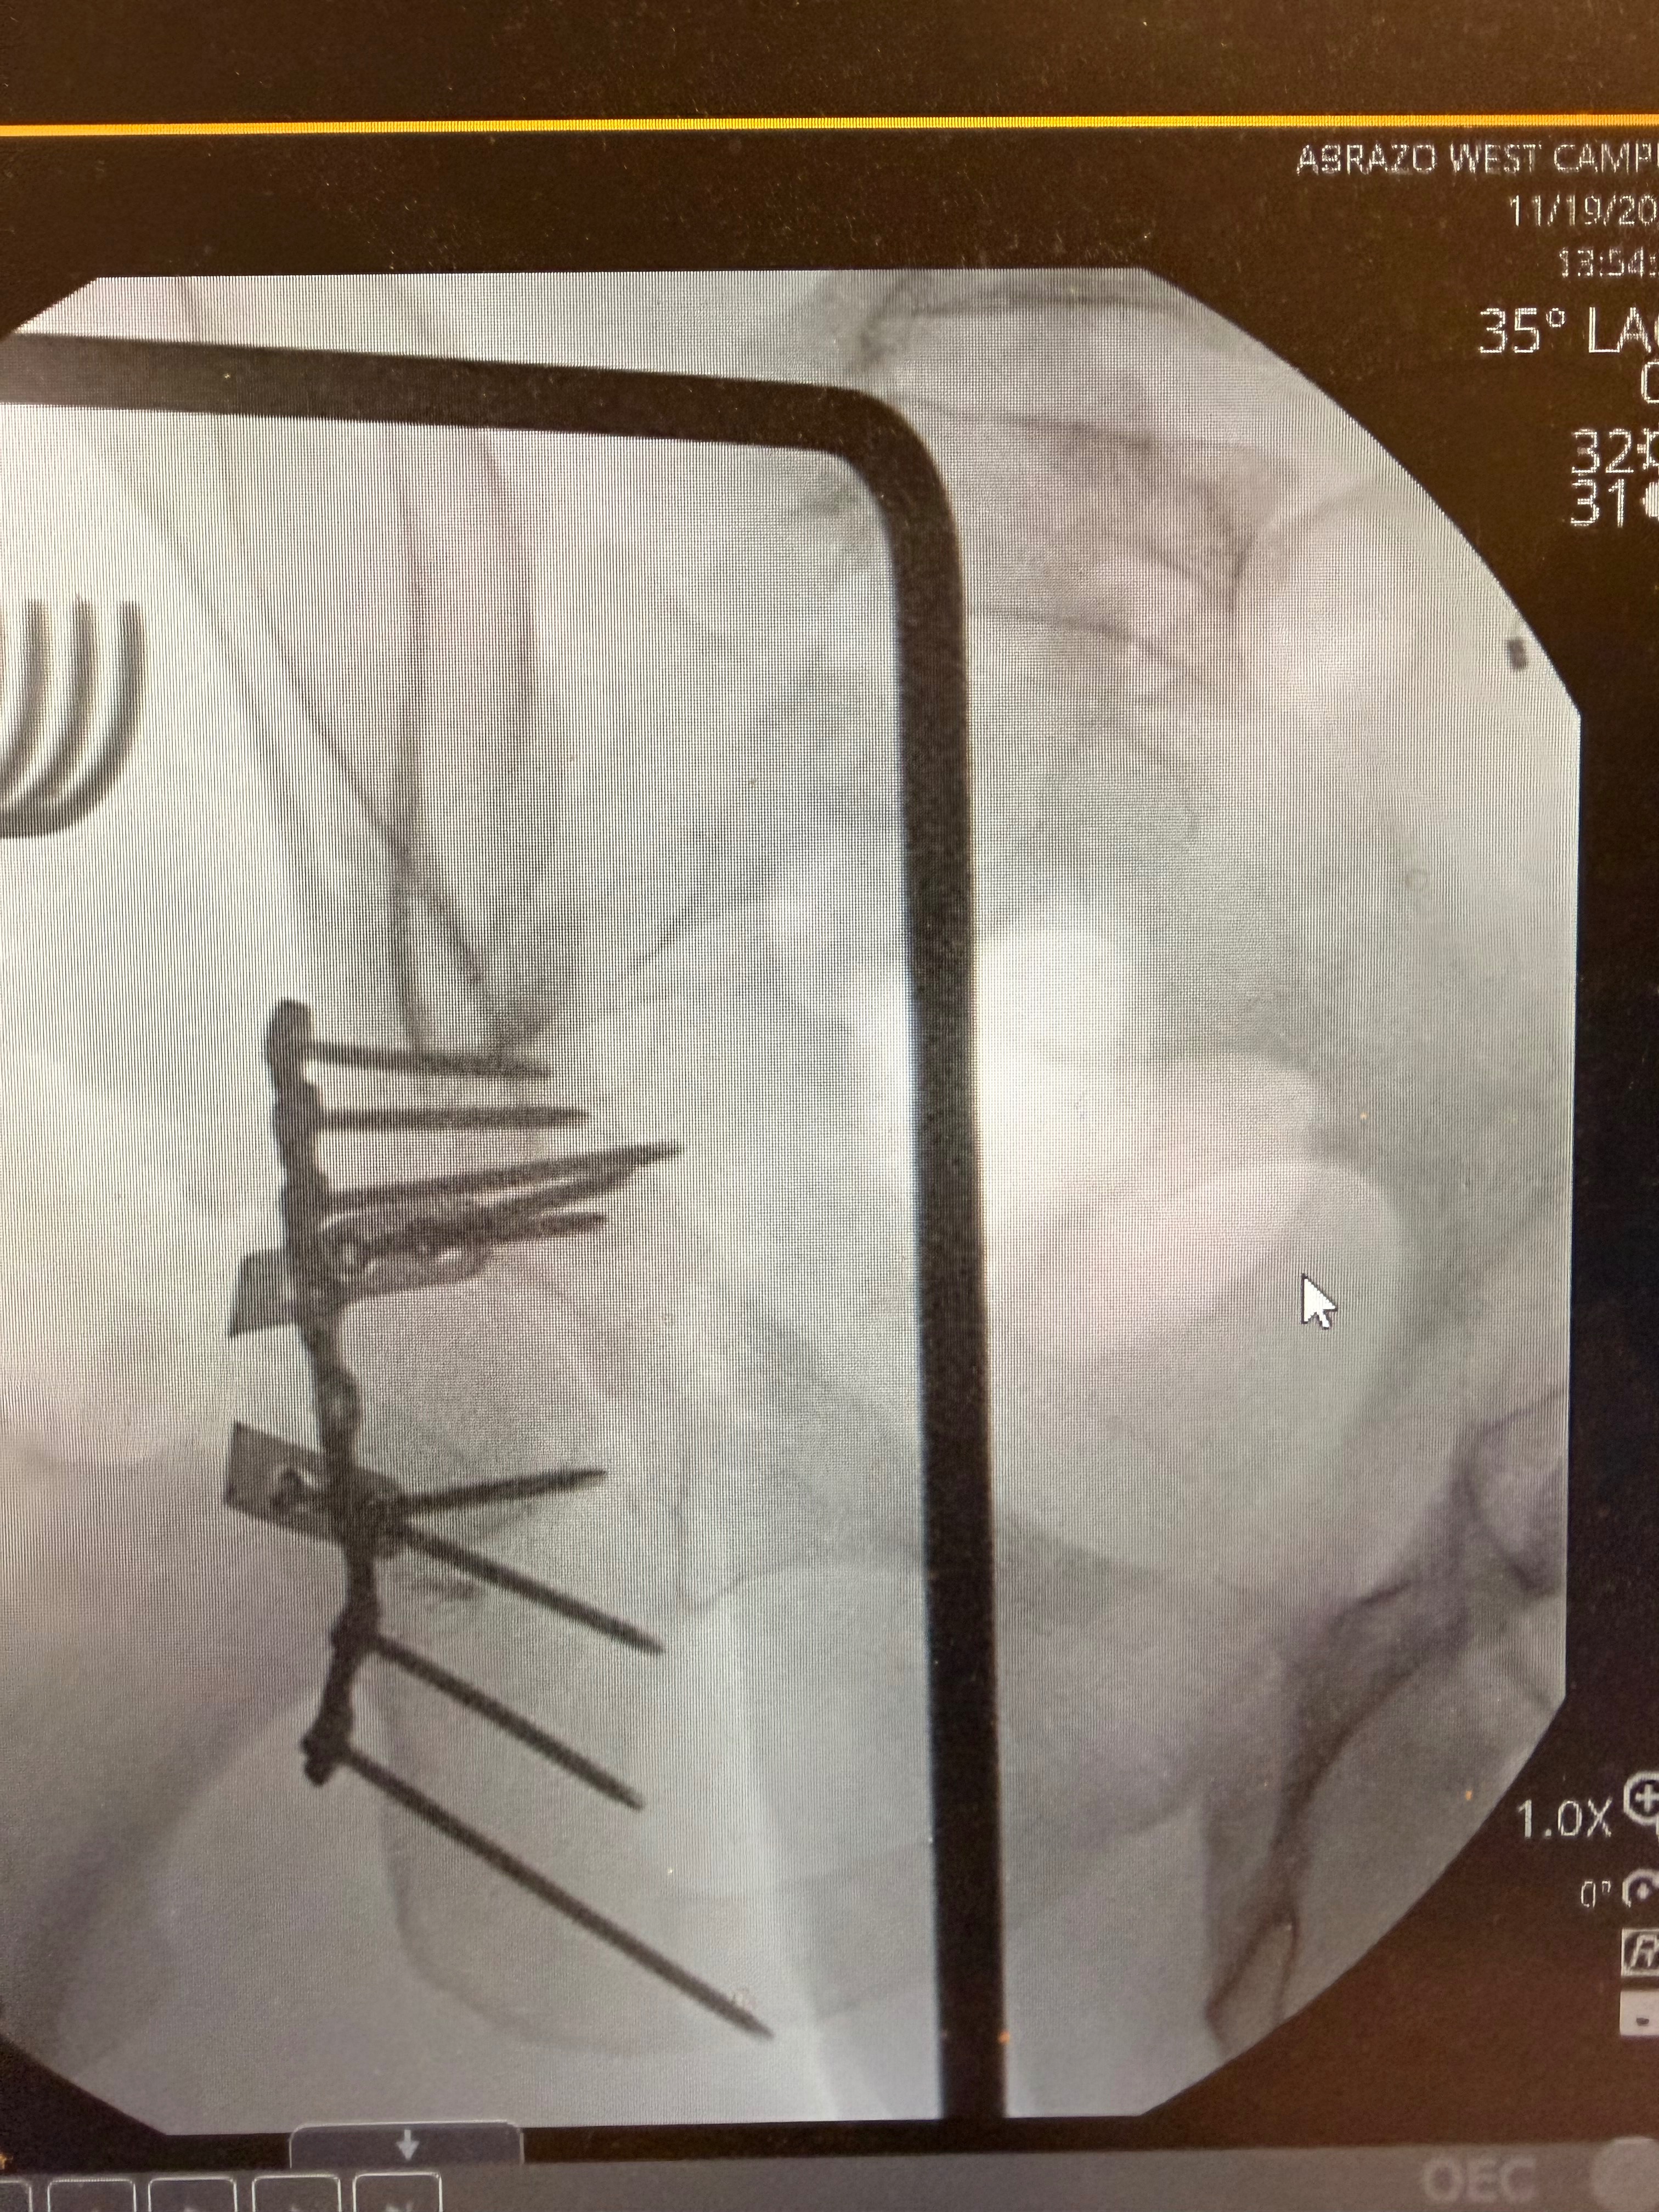

Recently, while training for his upcoming Freestyle Mania tour with Monster Jam, Billy suffered a devastating crash on his home setup. He shattered and dislocated his left hip, fractured his pelvis, and severed his sciatic nerve, leaving him with no mobility in his left foot. The road to recovery is long—doctors estimate 8 to 12 months—and during this time, Billy is unable to work. With no income, he’s facing mounting medical bills and the daily expenses of supporting Willow.